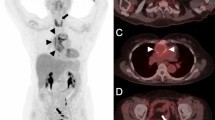

Of 10 patients who were treated for Takayasu arteritis, 4 showed evidence of aortitis on PET/CT scans; one of them also showed vasculitis in other large vessels. One patient's scan illustrated vasculitis in the infundibulum and pulmonary trunk alone. For 5 patients, no evidence of vasculitis was found. Of the 3 patients who had been treated for GCA, 1 had increased uptake along the abdominal aorta and along the great vessel superior, and inferior to the aorta bilaterally (Fig. 1). PET/CT scans of the remaining 2 patients did not show signs of active vasculitis.

Figure 1 Of 3 patients with a history of treated GPA, PET/CT studies revealed aortitis in 2. The PET/CT scans obtained from patients with HES, RA, PsO, Behçet's, and PCNSV demonstrated evidence of vasculitis in at least 2 large vessels. The scan from a patient with IgG4 disease displayed increased uptake in the large pulmonary arteries (Fig. 2).